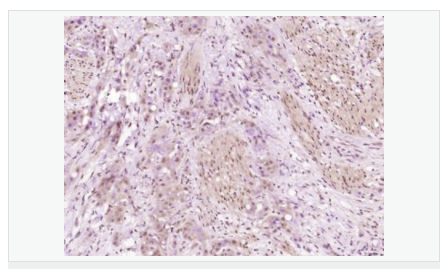

| 產(chǎn)品應(yīng)用 | WB=1:500-2000 ELISA=1:5000-10000 IHC-P=1:100-500 IHC-F=1:100-500 ICC=1:100-500 IF=1:100-500 (石蠟切片需做抗原修復(fù)) not yet tested in other applications. optimal dilutions/concentrations should be determined by the end user. |

| 細胞定位 | 細胞漿 細胞膜 |